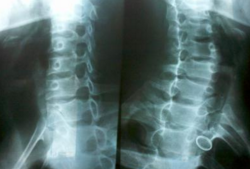

手机也是有辐射的,虽说不至于对身体有影响,但是长期下去会影响到人体的免疫力和智力发展,人就会特别容易疲惫;对于床上玩手机的人,很可能就是处于半躺的状态,这时颈椎就会承受过大的压力,对于青少年来说,在床上玩手机容易出现脊椎的弯曲,对于成年人来说也可能会出现脊椎病。

正常人的颈椎是生理弯曲,是正常的,但是如果往相反的方向弯曲我们就称为反弓,颈椎反弓是颈椎病中最为常见的,所以过高的枕头会增大下位颈椎的应力,加速颈椎的退变,如果靠在床上玩手机时间过长,长时间的牵拉颈椎会出导致曲线拉直,严重的还会出现反弓。由于玩手机导致我们的时间混乱,所以就会影响到我们的生物钟,对身体有很大的伤害;躺着玩手机手部供血就会不足,时间长了会导致手指或手臂的麻木。